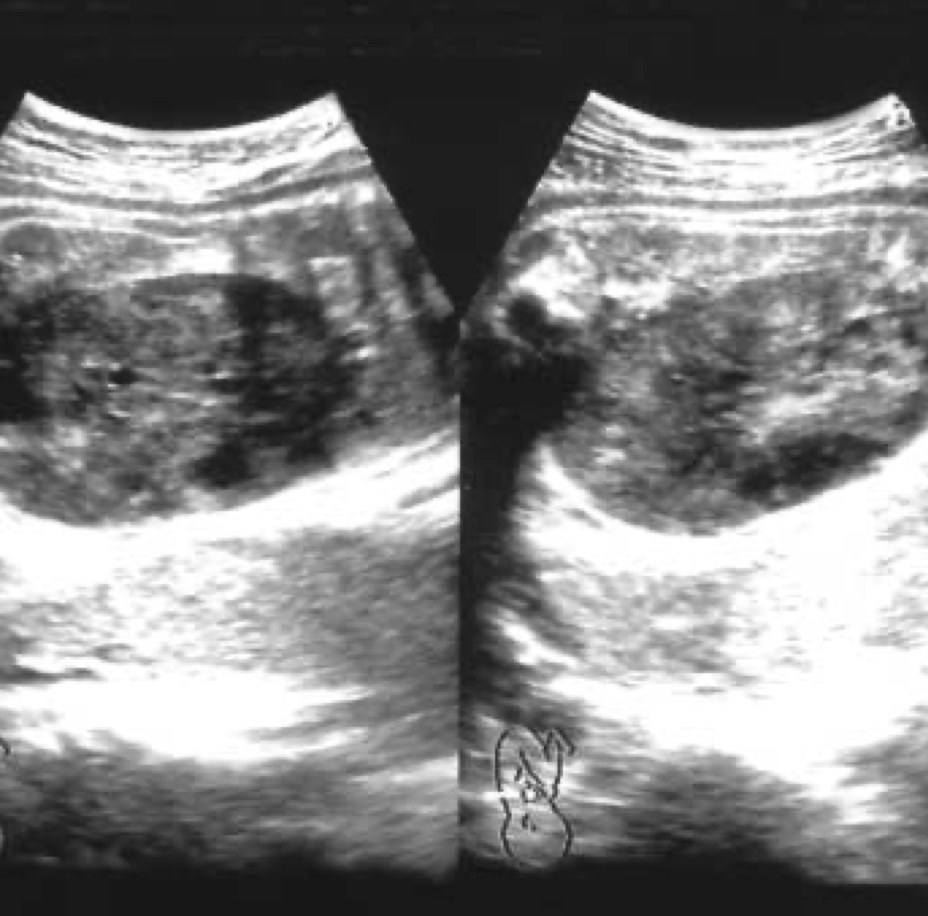

Upon admission to the NICU, the neonate exhibited a respiratiory rate 62/min, and blood pressure 69/43 mmHg. A physical examination revealed a prominent abdominal mass, measuring 7.5 cm in diameter on the right side of the abdomen, nearly occupying the abdominal cavity. The infant also presented with clubbed feet. Ultrasonographic examination and an abdominal CT scan unveiled a well-defined, heterogeneous, non-enhanced mass measuring 6.8 cm in diameter, originating from the right kidney, displaying both necrotic and cystic components. The left kidney appeared normal.

Sonographically, mesoblastic nephroma may present as a large (4 to 8 cm), unilateral renal mass with nodular densities, or as diffuse renal enlargement. These tumors are predominantly solid, but cystic areas are occasionally seen. Unlike Wilms’ tumor, there is no well-defined capsule, most likely due to hemorrhage with subsequent cystic degeneration.